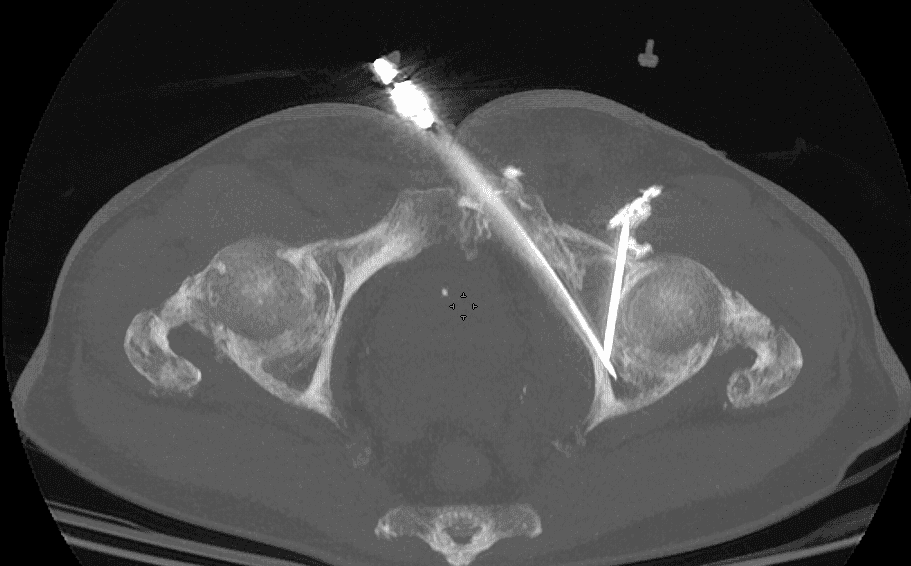

Insertion et déploiement du matériel d’ostéosynthèse :

Une fois l’aiguille positionnée, le vissage est réalisé en respectant la trajectoire prédéfinie, permettant de réaligner les fragments osseux.

Le vissage est ensuite fixé de manière à assurer une stabilité mécanique suffisante pour supporter les contraintes de la zone cotyloïdienne.

Un contrôle scanner final permet de vérifier la position du vissage et la qualité de la réduction anatomique, garantissant ainsi le succès de l’intervention.